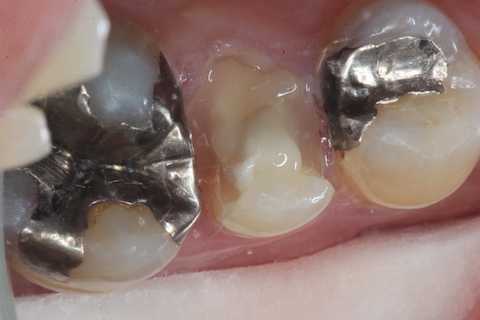

今日の充填治療56(メタルインレー脱離) 2025.01.04